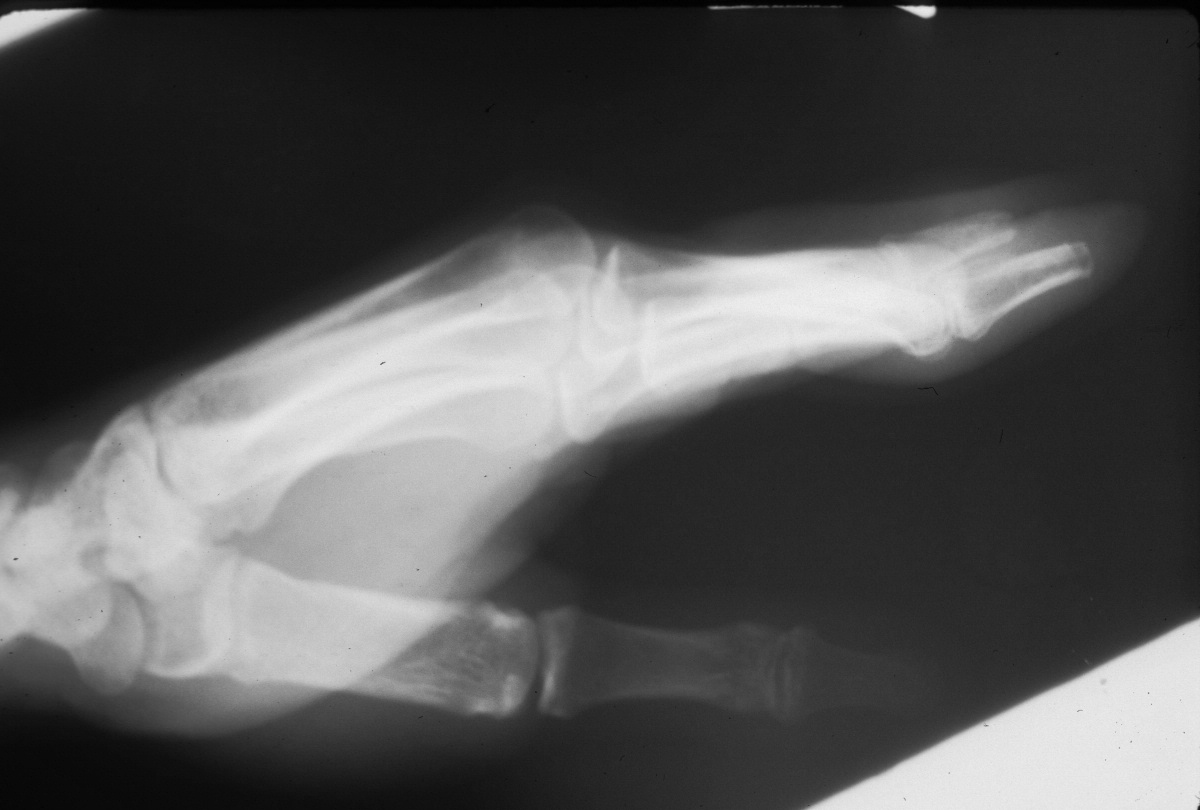

Clinical Example: Multiple finger degloving treated with medial cross arm flap and temporary syndactyly

Degloving injuries are commonly the result of industrial injuries involving high speed rollers or presses. Reconstruction is difficult because of the complexity of soft tissue loss. Skeletal elements maintain vascularity only to the most proximal phalanx distal to the most proximally degloved joint, and more distal phalanges should be discarded. This case demonstrates the first stages of reconstruction of a degloving injury of all fingers using a medial cross arm flap and temporary syndactyly within the flap.

Initial injury: